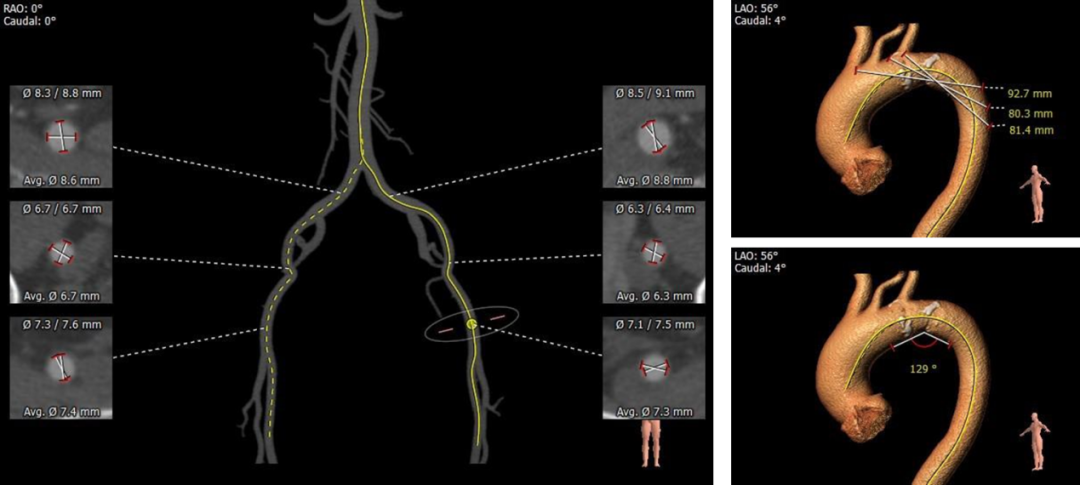

1.主动脉瓣瓣环周长69.0mm,平均周长径22.0mm。

2.Type0型二叶式主动脉瓣,左右冠不同窦,重度钙化,钙化分布欠均匀,右冠瓣尤甚,主要分布于瓣叶边缘及管壁附着缘,瓣叶增生肥厚。

3.左右冠开口高度较高,未见明显钙化,右冠瓣叶长度>右冠开口到右冠瓣叶附着缘距离。

4.瓦氏窦内径尚可,窦管交界内径可,升主动脉无扩张,LVOT内径大于瓣环,呈火山口状。

5.左室腔内径可,心室壁不厚。主动脉瓣环与水平面夹角54°,主动脉弓部夹角与弓距可。

6.双侧髂动脉未见明显钙化及扭曲,双侧股动脉穿刺区域未见钙化斑块,主动脉弓少许钙化,双侧血管内径可。

主动脉根部评估:

根部概览

左室

瓣环上解剖结构评估

外周血管及主动脉弓解剖:

1.推荐右侧股动脉为主入路,左侧辅助入路,推荐20F血管鞘

2.根据当前影像资料及测量数据,推荐跨瓣角度为LAO 20° CAU22°(双窦展开)左右

3.推荐选择18mm球囊预扩张,推荐球囊预扩角度为LAO 20° CAU22°(双窦展开)左右,推荐预装AV23瓣膜

4.瓣膜释放角度为LAO 20° CAU22°(双窦展开)左右,释放高度推荐瓣环下0--2mm左右。释放后建议调整至足位(RAO 15° CRA28° )进一步确定人工瓣膜形态。上述角度仅供参考,因体位变化及心动周期等原因,术中实际角度会存在偏差,具体情况由手术实际进行选择